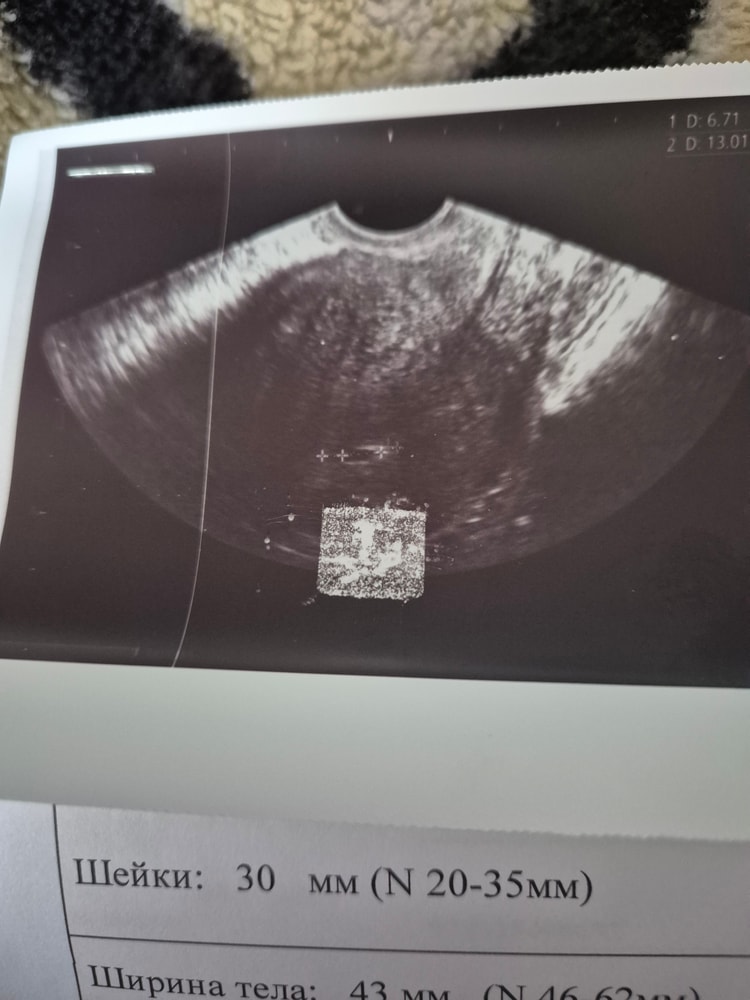

Девочки добрый день,сдала узи на 21 день после переноса. Доктор сказал что на неделю отстаёт, только пдодное яйцо видно. Эмбриона пока не видно. У кого так было поделитесь пожалуйста. Это 4 перенос крио.